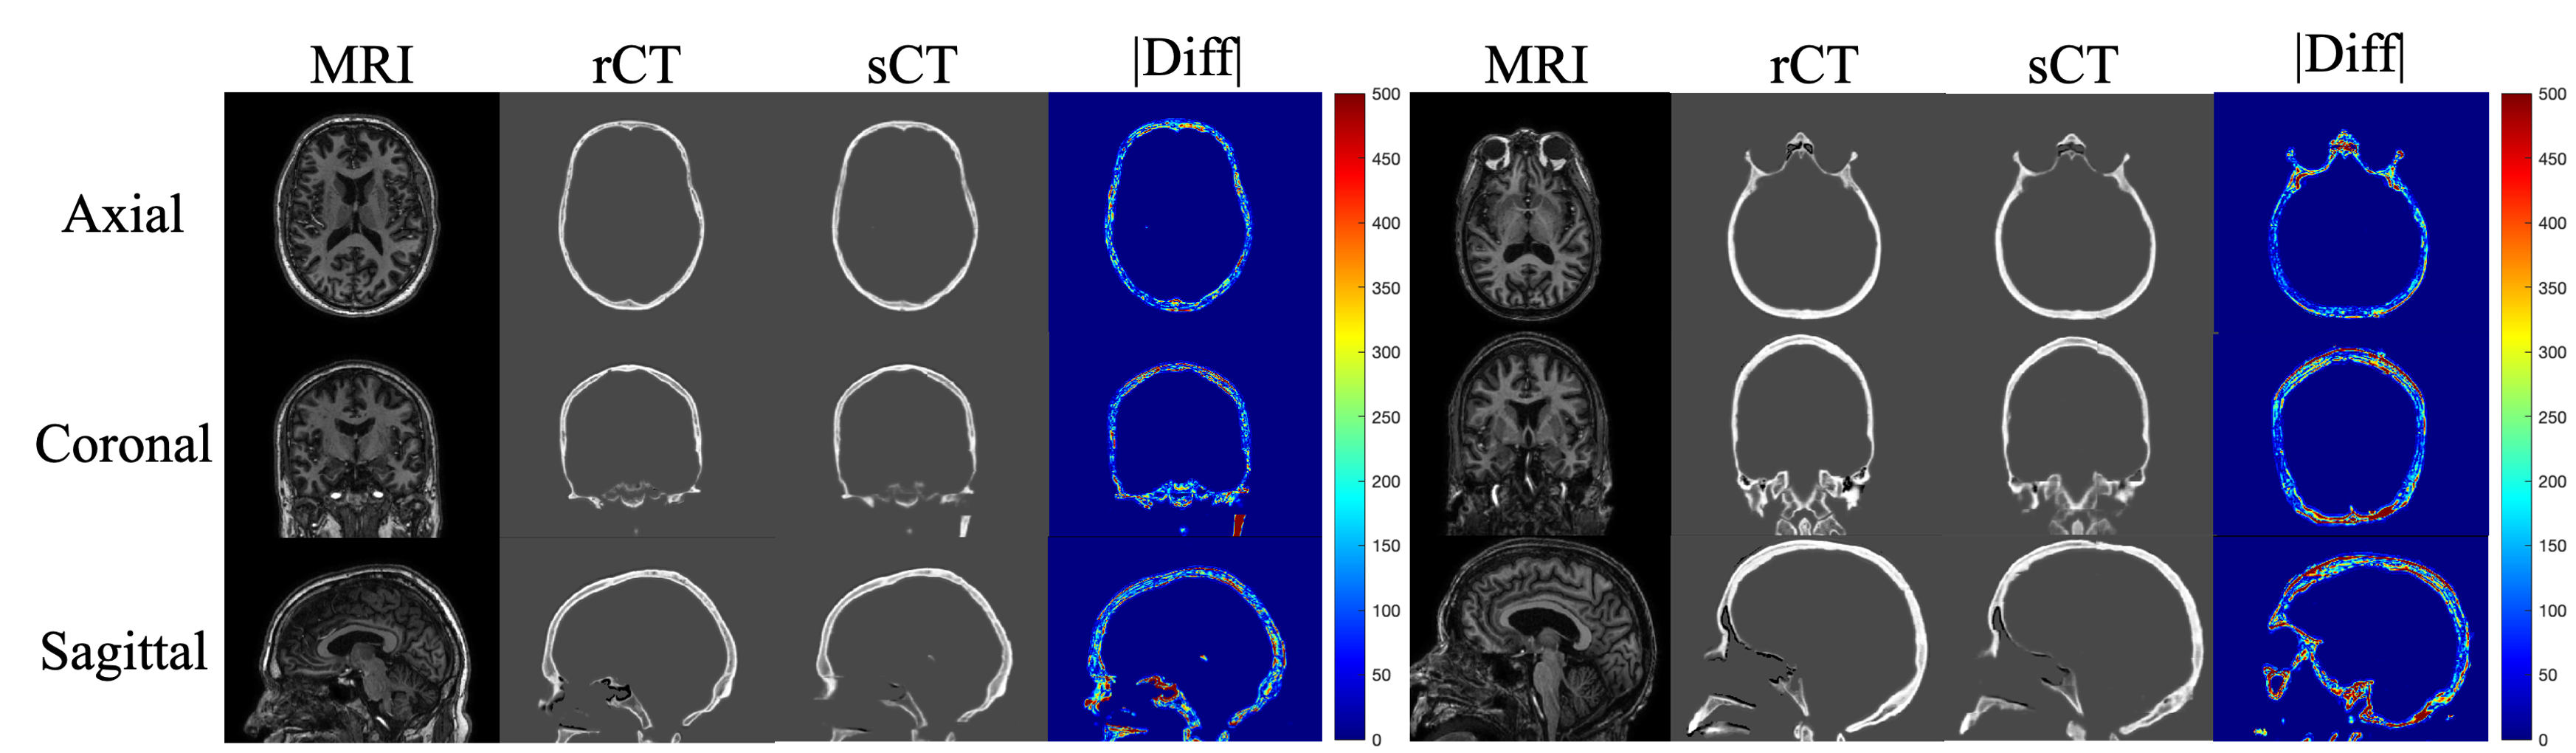

Figure 2: Examples of the original T1-weighted MRI, real CT (rCT), synthetic CT (sCT) and absolute difference map (|||diff|||). The two subjects with MAE of 157.98 HU (left) and 233.76 HU (right) in the skull regions are shown. For visualization purpose, we rescaled the difference heatmap to [0,500]0500[0,500] HU. Notice that the bones in the inferior brain area tend to have a larger difference.

In our testing set, the MAE between rCTs and sCTs in skull regions was 190.94±22.40plus-or-minus190.9422.40190.94\pm 22.40 HU. Absolute difference heatmaps for test cases with the smallest and largest MAE exhibited larger MAE at the inferior part of the skull than the superior part (Figure 2). Note that we used 3D networks and thus our synthesized skulls were spatially continuous in all views.